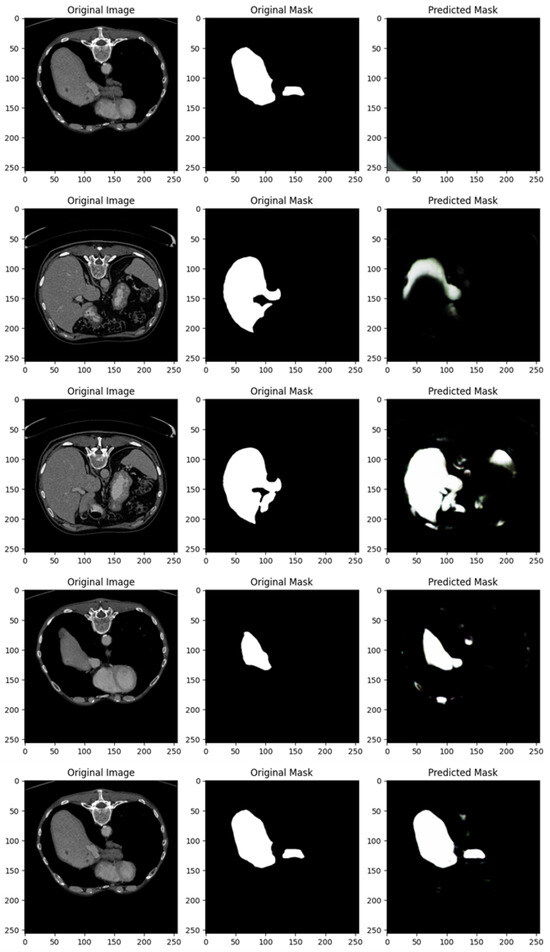

Figure 4 shows the segmentation capabilities every 25 epochs (for the first 100 epochs) of the U-Net model trained with the DI dataset.

Figure 4 shows, for different epochs, a set of images with the related segmentation mask predicted at a certain epoch. In particular, it shows the original images, original masks (i.e., the ground truth) and the predicted masks generated by a U-Net network trained for different numbers of epochs (1, 25, 50, 75, and 100 from top to bottom). The aim of the U-Net network is likely to segment a specific region of interest in the abdominal CT scans, i.e., the liver, based on the shape of the masks.

In the following, we provide a detailed analysis of the several masks generated for each epoch considered in Figure 4.

At 1 epoch, the original abdominal CT scan clearly shows several internal structures. The original mask marks the liver region in white, indicating its precise location and shape. However, the predicted mask is empty, suggesting that the U-Net model has not yet learned to recognize and segment the liver region. This is expected, as early stages of training often result in poor or no predictions.

At 25 epochs, the model begins to show some improvement. The original image is another abdominal CT slice, displaying a similar view. The liver region is again marked in white in the original mask, now with a small additional structure. The predicted mask, although incomplete and somewhat noisy, shows a partial segmentation of the liver. The areas predicted by the model are highlighted in pink, indicating that while there is some correspondence with the original mask, the model is still in the process of learning to isolate the liver region correctly.

By 50 epochs, the model’s performance significantly improves. The original image is another abdominal slice, and the liver, along with a small adjacent structure, is clearly demarcated in the original mask. The predicted mask now captures a larger portion of the liver, though there is still some noise around the region, signaling that the model is not yet fully refined. However, it has made substantial progress in recognizing and outlining the liver.

At 75 epochs, the model’s segmentation is much more accurate. The original image remains consistent with the others in this set. The liver region is again highlighted with a small additional white structure in the original mask. The predicted mask now closely approximates the shape of the liver shown in the original mask, with minimal noise. The model has become much better at distinguishing the target region, though a small amount of excess segmentation remains, indicating that further refinement is possible.

At 100 epochs, a new abdominal slice is introduced. However, this slice does not have an original mask, possibly indicating a different region or a non-target slice. The predicted mask is empty, similar to the prediction after 1 epoch. Since the original mask is missing, this suggests that the model is either not designed to segment this specific structure or has successfully learned not to apply a mask where no liver structure is expected.

As shown from Figure 4, as the number of epochs increases, the U-Net network demonstrates clear improvement in segmenting the liver. At 1 epoch, the model has no predictive capability. By 25 epochs, it starts to recognize relevant areas but is still noisy. From 50 epochs onward, the predicted masks align more closely with the original masks, with improved segmentation accuracy and reduced noise. The model at 100 epochs demonstrates the ability to avoid unnecessary predictions in slices where no liver is present, indicating the model has generalized better.

Training the U-Net model over more epochs results in significant improvements in segmentation quality, with the model learning to more accurately capture the target region (liver) and minimize noise. By 75 epochs, the predictions are highly accurate, and by 100 epochs, the model shows the ability to generalize to slices where no segmentation is required, which is a sign of good model training.